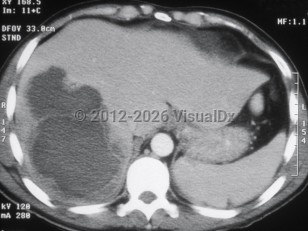

Laboratory evaluation reveals leukocytosis, elevated transaminases, and elevated alkaline phosphatase. The abscess can be visualized by computed tomography or ultrasound. Usually only one lesion is seen. Most of the time, the lesion is located in the right lobe of the liver.